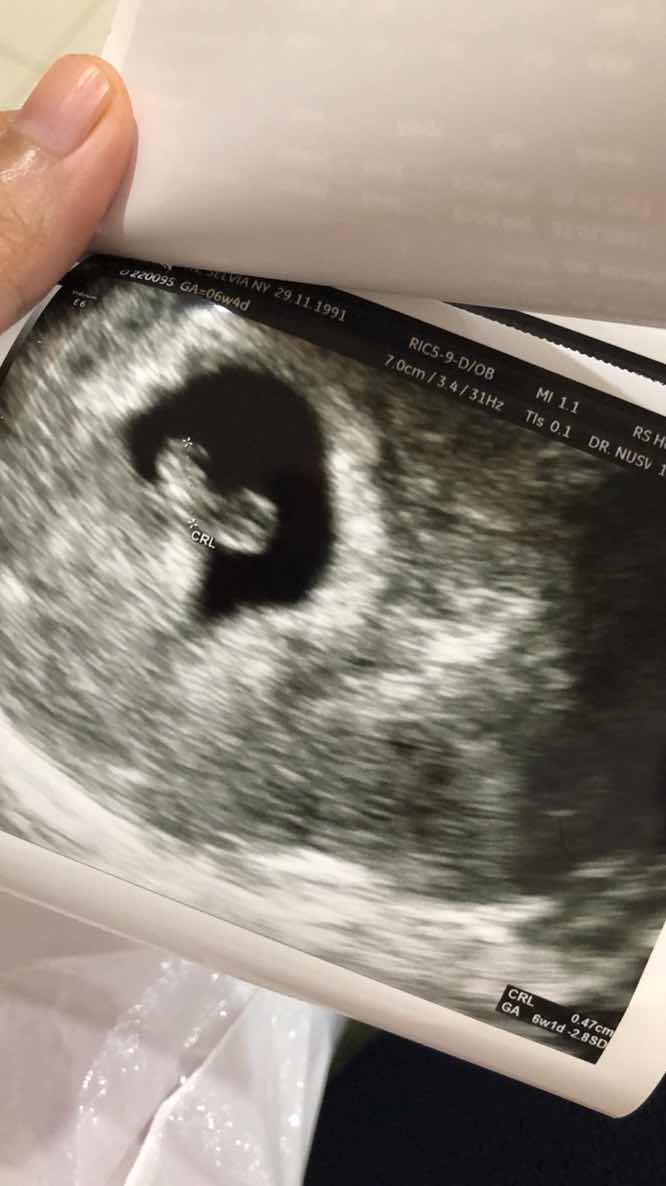

Alhmdulillah saya sudab hamil 6 minggu 4 hari dan sudah USG detak jantung janin sudah terdengar dan alhamdulillah sehat, tapi kendala yang saya alami..

kendala yang saya alami saya sering flek awalnya cuman segaris dua garis smpai hari ini banyak seperti halangan, dan saya cek ke dokter “ ada byak darah dibelakang ketuban” karena kurang istrhat sehingga disuruh bed rest selama sebulan, apakah ada yang ngalamin seperti saya bunda ? selama bed rest bunda ngapain aja ?